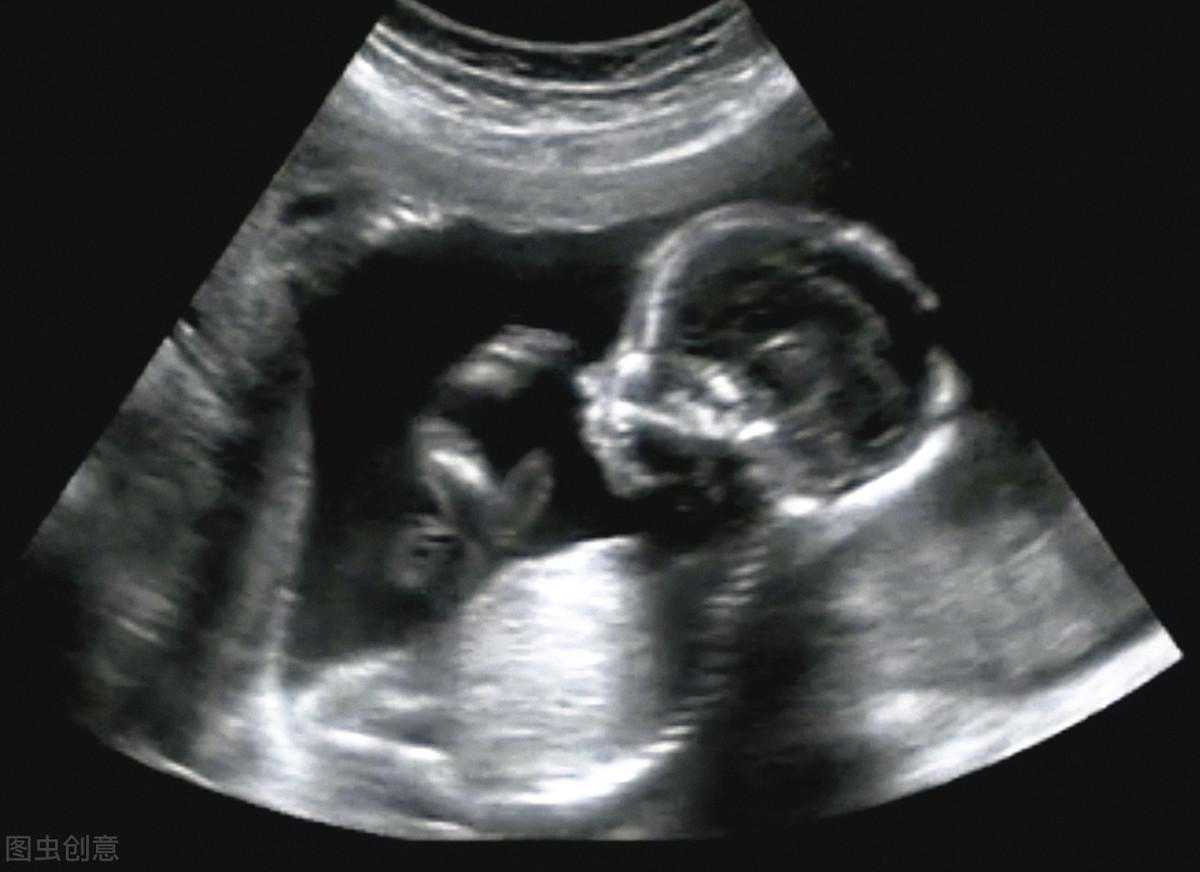

四维彩超的功能①四维彩超不仅可以观察宝宝形态,了解胎儿基本信息如呼吸及运动等。

②准爸妈可以亲眼目睹宝宝的一举一动和乖巧笑容。

③为众多的准妈妈们增添无数安心和情趣。

④四维彩超从专业角度多方位、多角度地观察宫内胎儿的生长发育情况。

⑤为早期诊断胎儿先天性体表畸形以及先天性心脏疾病提供准确的科学依据。

四维超声为何一次检查不过关?宝宝不翻身,医生拍不到检查角度,看不到正脸,眼睛、鼻子、嘴、胳膊、手指及腿和脚趾,无法排查畸形。

“宝宝总是趴着,或者用手挡住脸部”,这种就算是不配合检查了,遇到这种情况来回检查2-3趟再正常不过了。